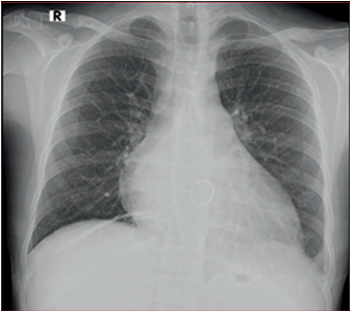

La radiografía de tórax mostró cardiomegalia con participación ventricular izquierda y biauricular, arco medio izquierdo prominente, prótesis valvular en proyección mitral, signos de hipertensión venocapilar pulmonar y leve derrame pleural izquierdo (Figura 2).

Figura 2 Obliteración de fondo de saco costo diafragmá tico lateral izquierdo. Redistribución de flujo a vértices. Índice cardiotorácico aumentado.